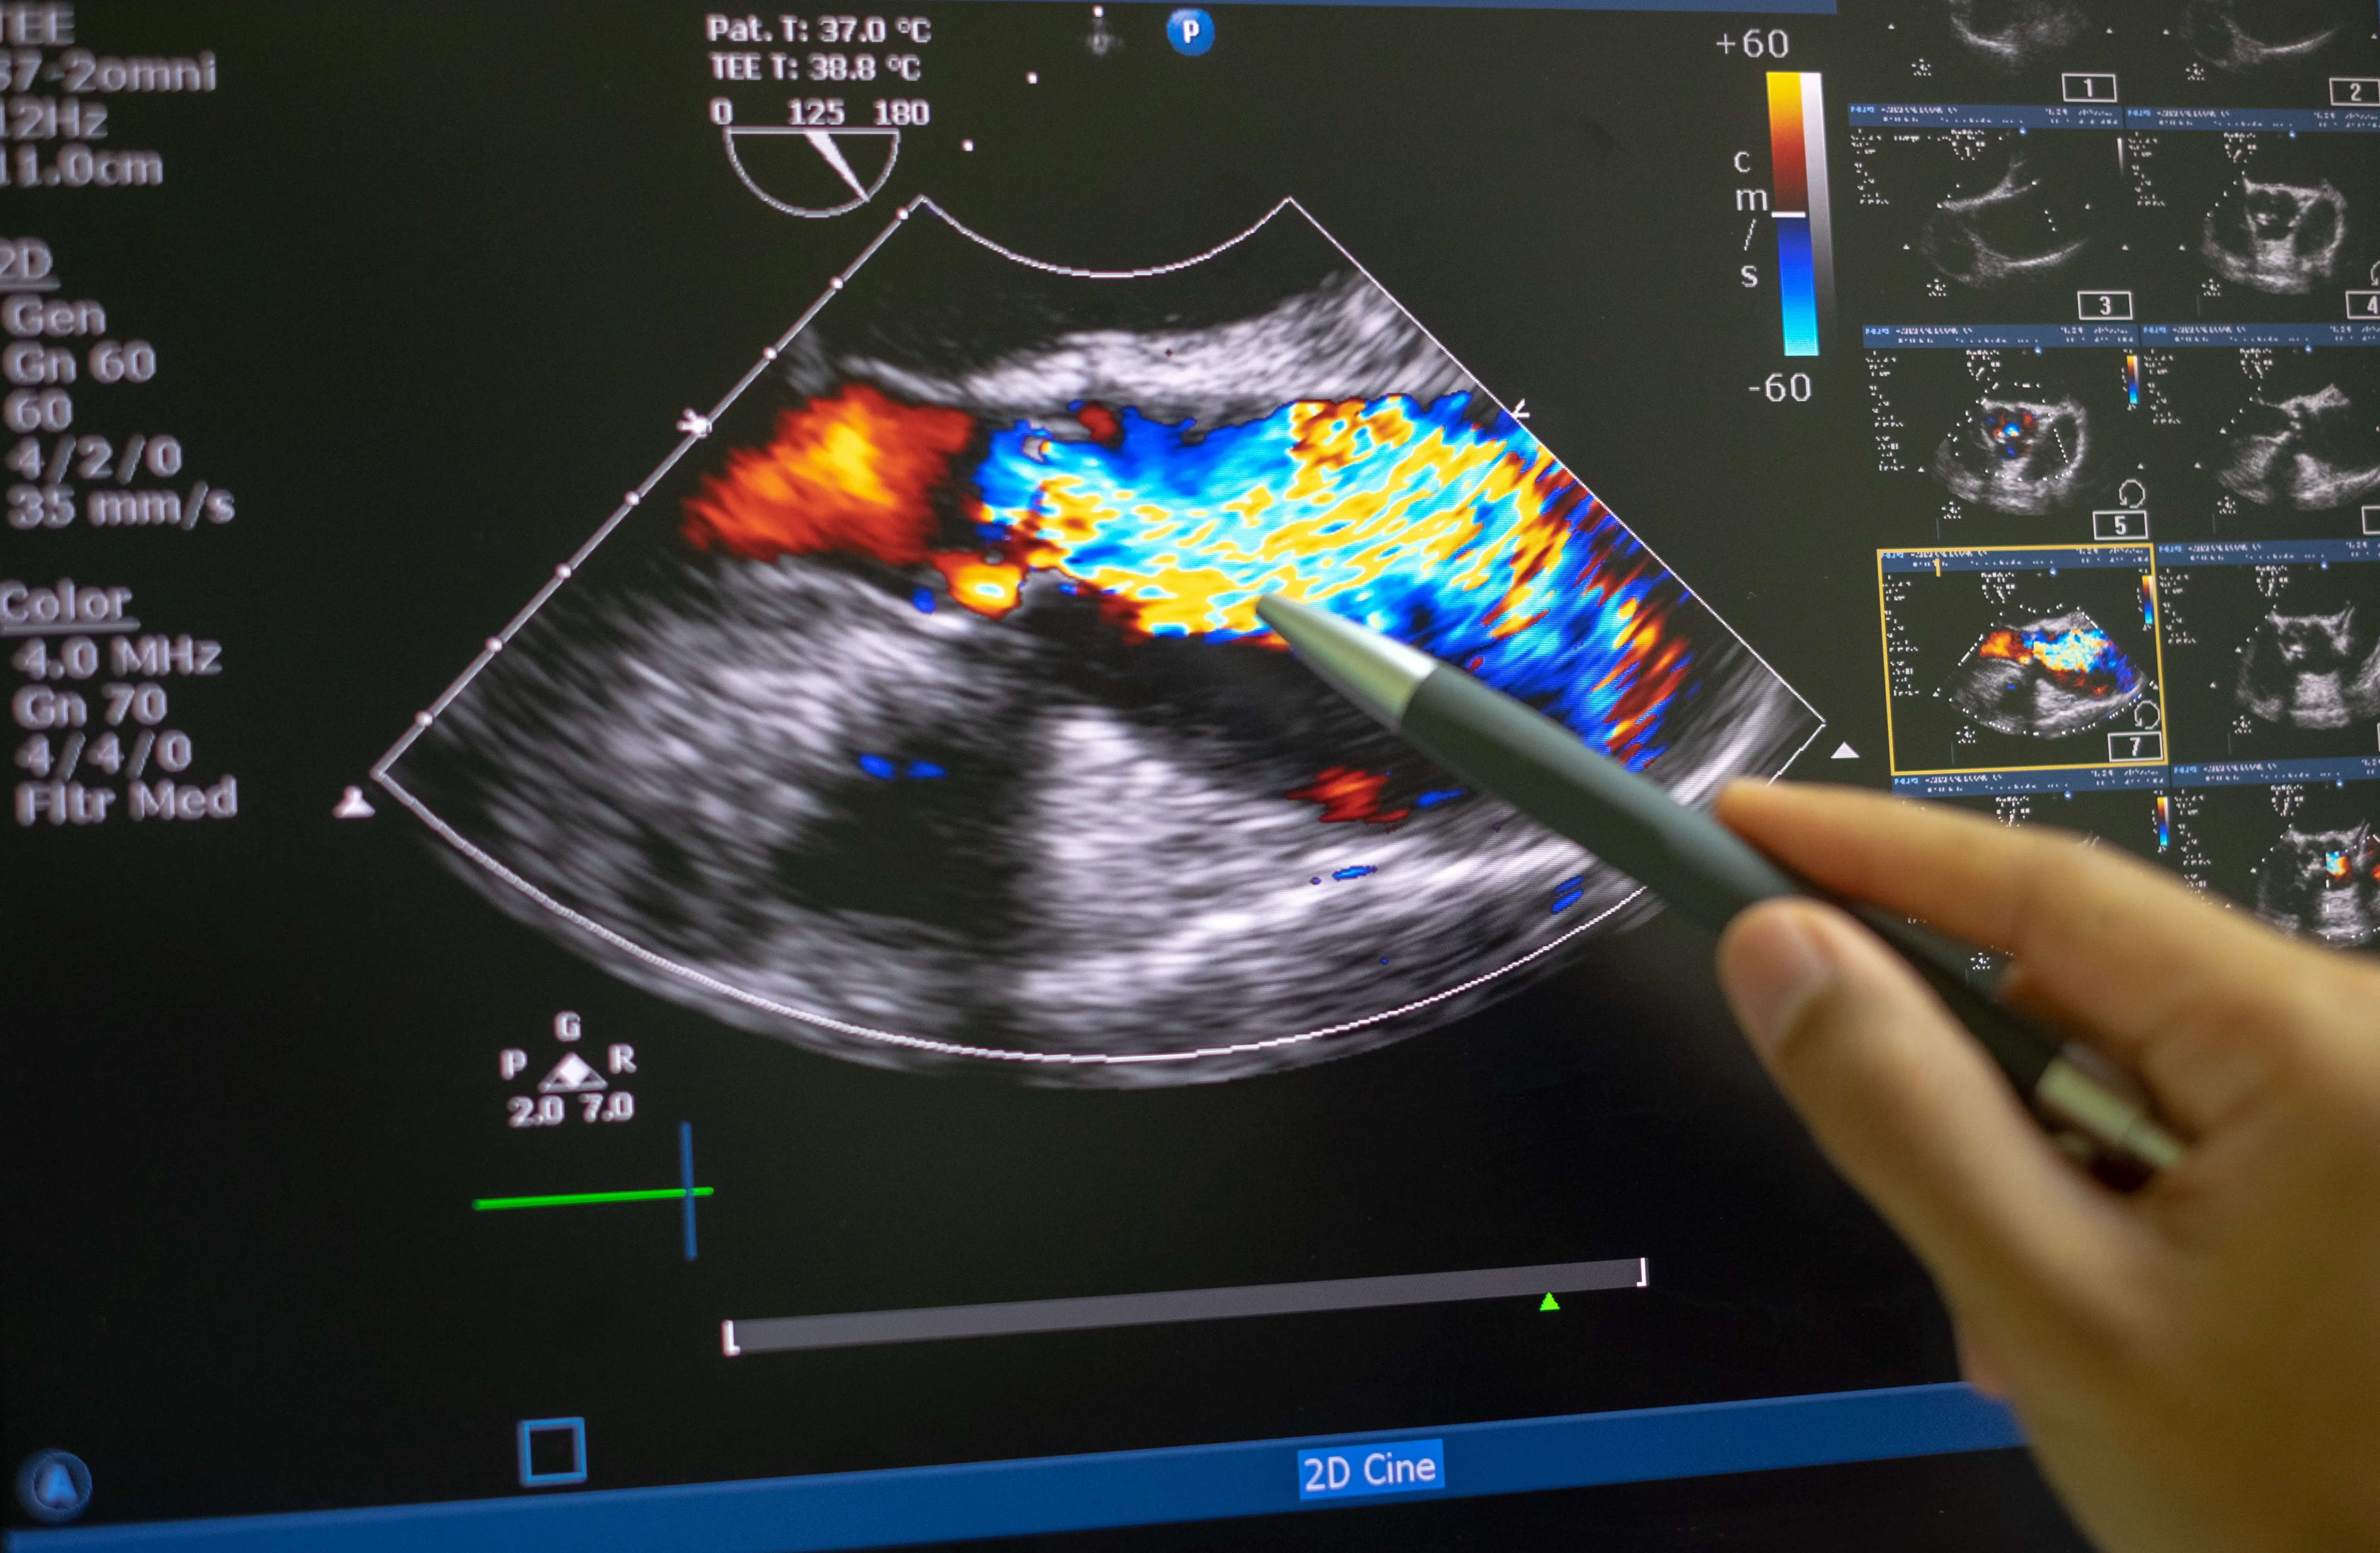

Kalp Kapak Hastalıkları: türleri, belirtileri, teşhis (EKO, EKG) ve ilaç, girişimsel ile cerrahi tedavi seçeneklerini kapsamlıca öğrenin.